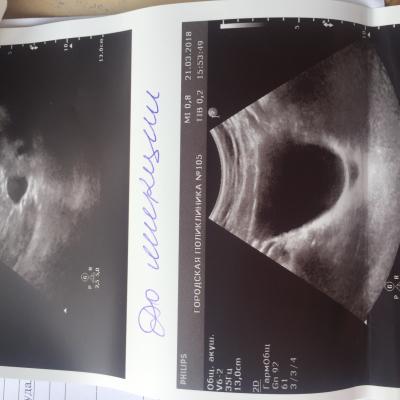

Здравствуйте. С Рождения гидронефроз левой почки , была удалена в декабре 2009 года. Анализы мочи и биохим анализ крови все показатели всегда в норме. Ребёнку 8 лет, сейчас одно УЗИ показывает размер почки 112 на 56, лоханка 16 мм. Другое узи сделанное через день показало: размер почки 78 на 30 , лоханка 7 мм. Паренхима на обоих узи 13 мм. Так же было сделано исследование УЗДГ почки ( все в норме, отклонений нет) Не можем понять почему такая разница по УЗИ где правда ? Как нам с этим разобраться .